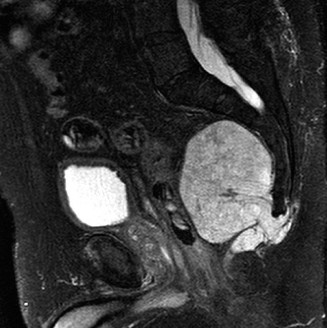

A 52-year-old female is referred from her primary care physician’s office. She has had vague lower back pain …